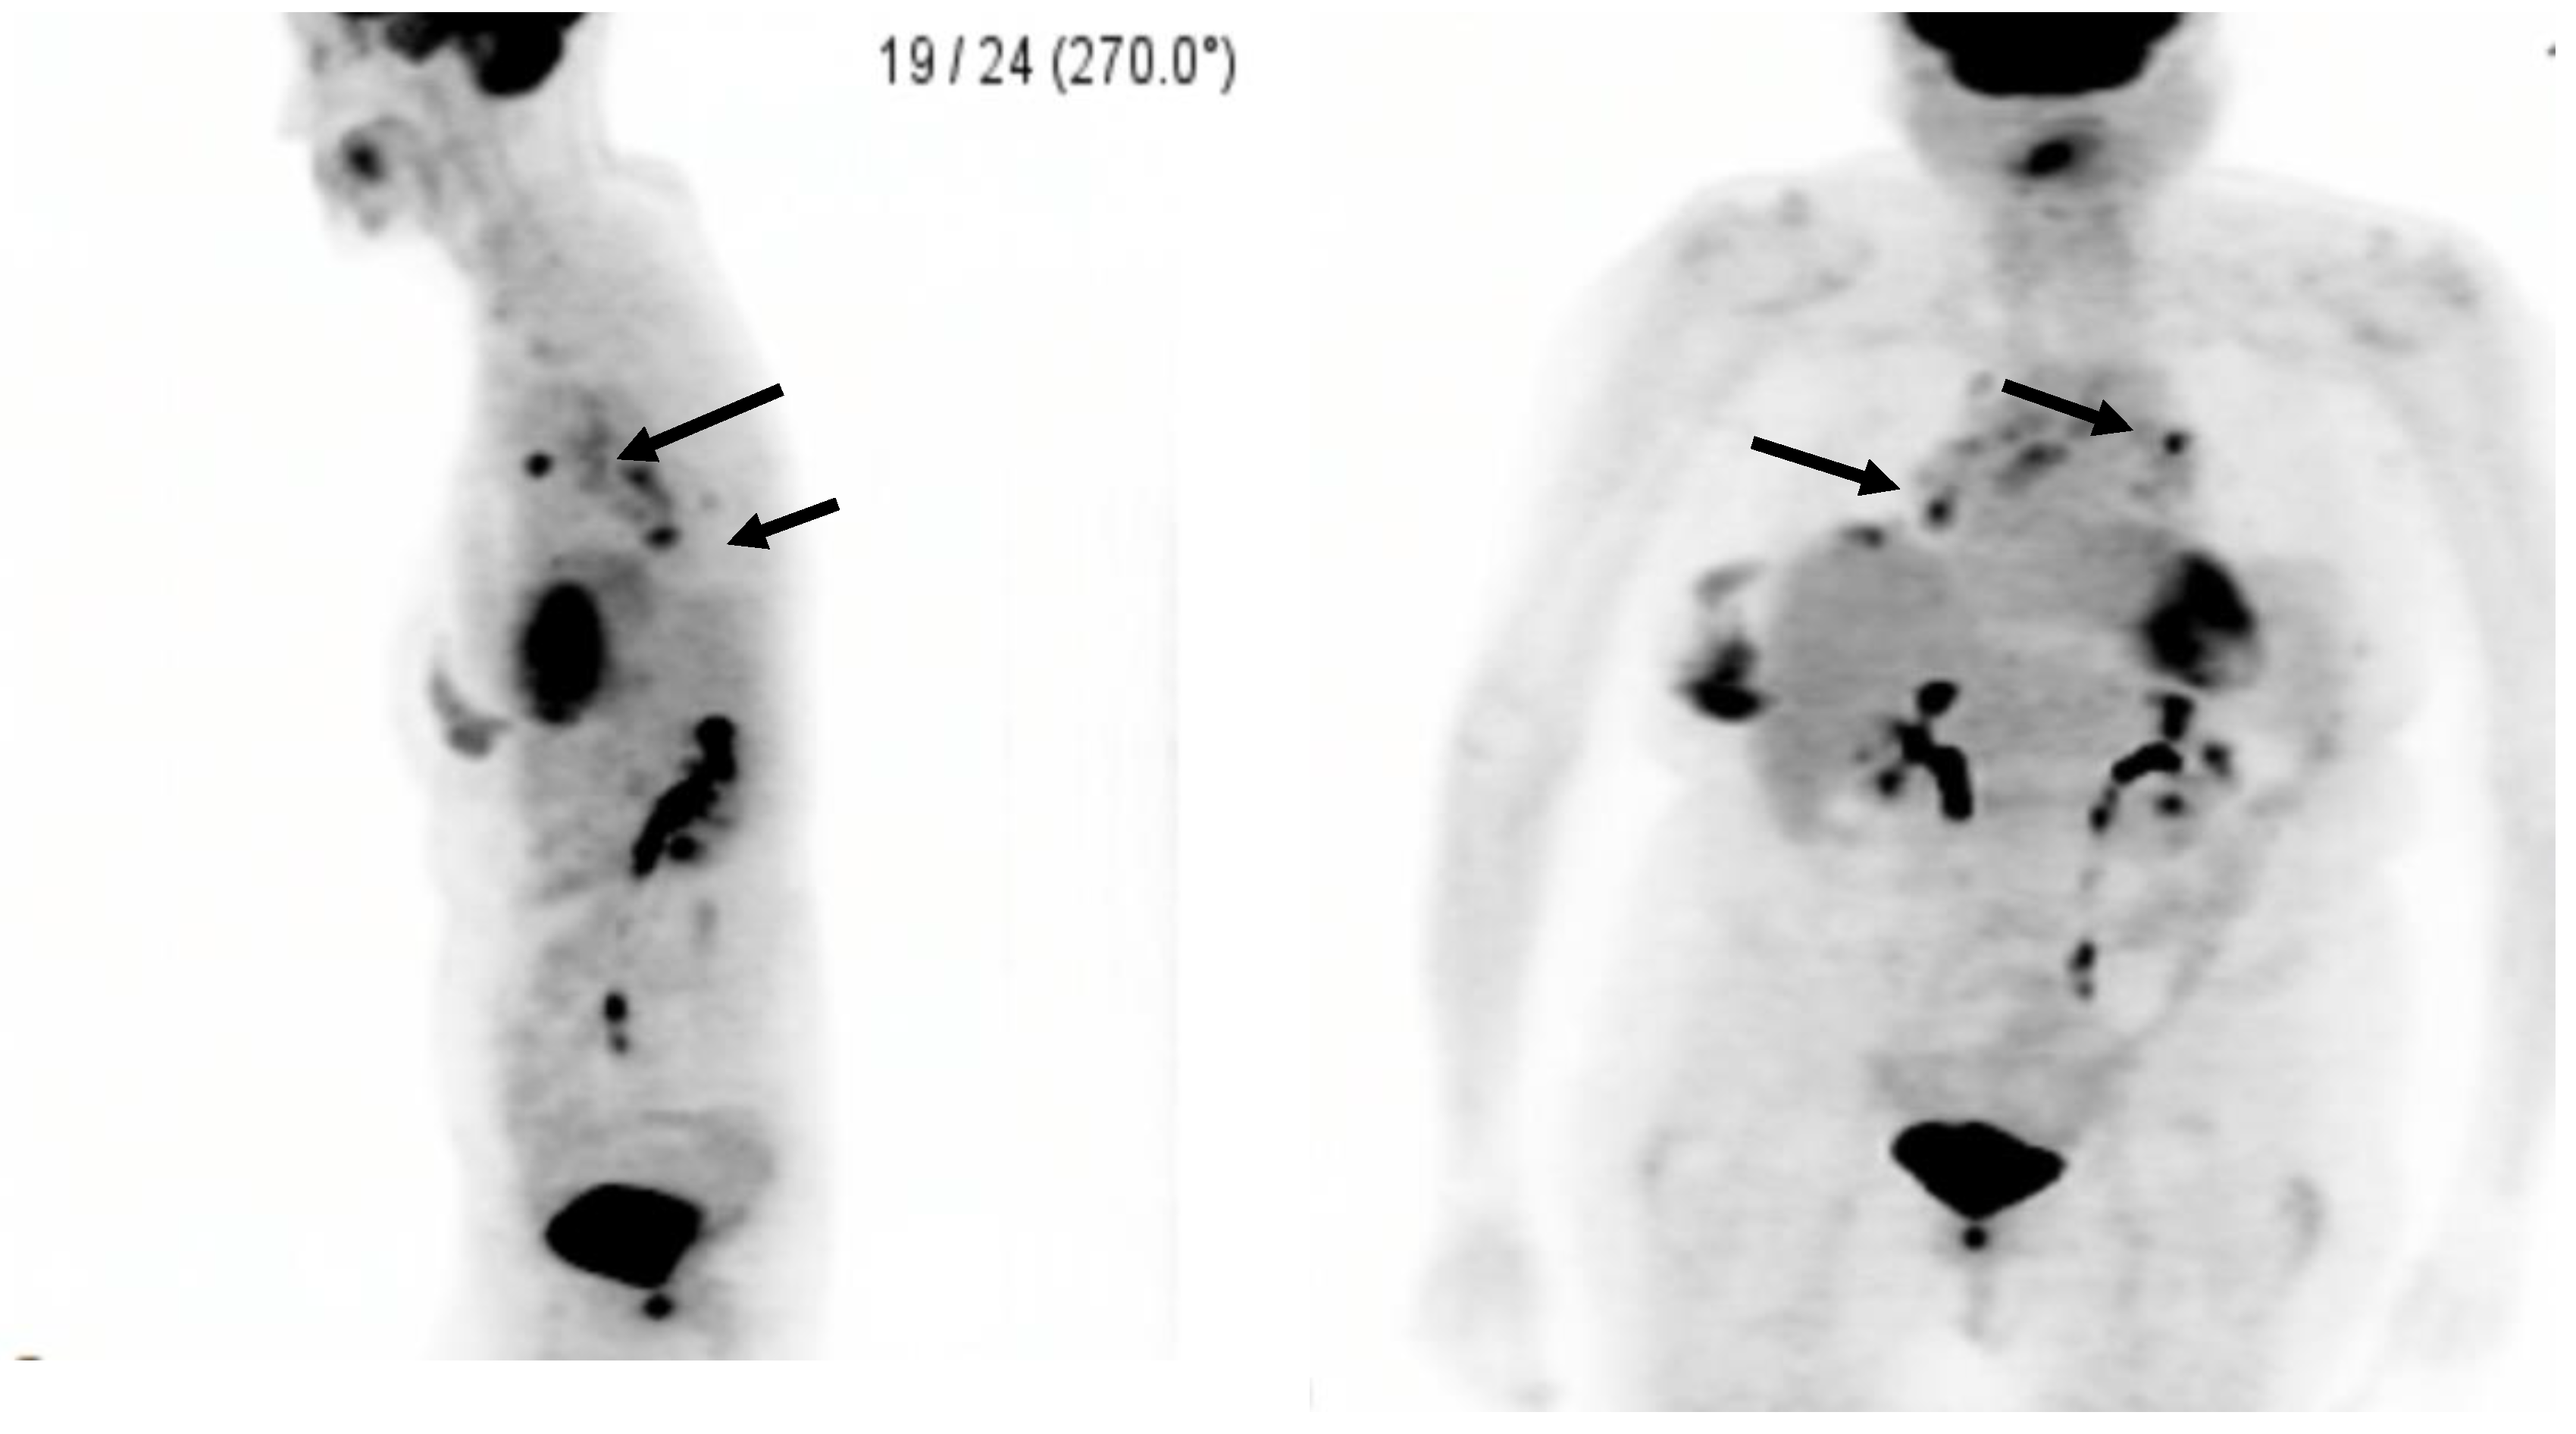

Not All That Shines on a PET Scan Is Cancer: A Silicone-Induced Granuloma Masquerading as Malignancy